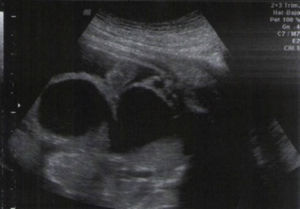

Historia clínicaSe trata de una paciente de 17 horas de nacida, que fue remitida con diagnóstico de recién nacida prematura de 35 semanas de gestación, con megalouréter y malformación de la vejiga, con antecedente de ascitis fetal (fig. 1). Durante la gestación se practicó amnioscentesis, el cariotipo fue normal y los estudios para TORCH fueron negativos.

Ecografia obstétrica. Corte coronal del feto, en el que se observa una imagen quística de pared gruesa, comunicada con lo que pareciera corresponder a la vejiga; se sospecha megauréter y megavejiga. Nótese el líquido libre en cavidad abdominal. En la evaluación retrospectiva, las imágenes quísticas observadas probablemente correspondían al cuello uterino (a la derecha de la imagen) y al útero (a la izquierda), distendidos por material mucoide.